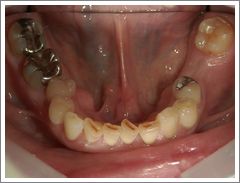

症例 10 下の奥歯に対してインプラント治療をして咬めるようになったケース

治療前

過去に右下奥歯2本を失い、右側でしっかりと咬むことができなかった方です。

入れ歯ではしっかりと咬めず、違和感が強かったため、インプラント治療を希望されました。

インプラント治療によって右側でもしっかりと咬むことができるようになり、満足して食事をしていただいています。 ( 50代 男性 )